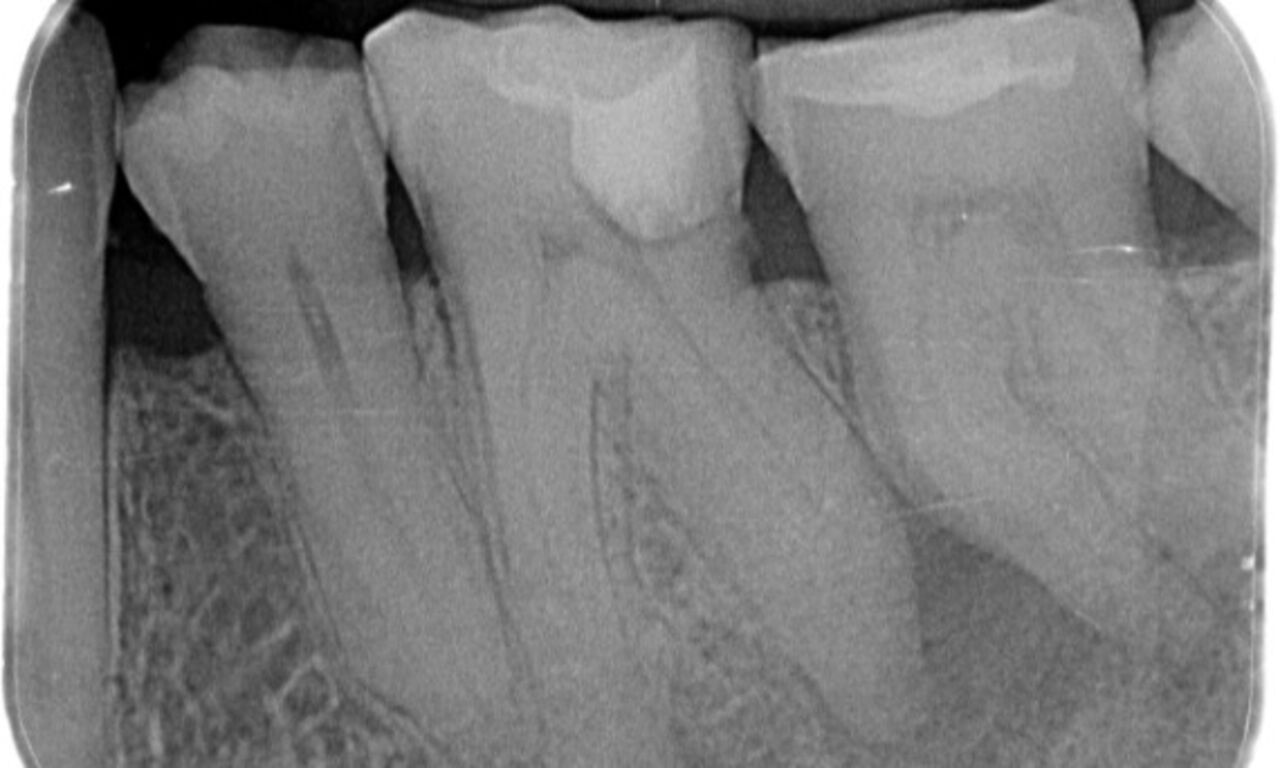

Periapical radiolucency associated primarily with the distal root and loss of lamina dura on the mesial root.

TruNatomy was chosen in this case to allow a caries leveraged approach and a focus on pericervical dentin preservation especially on the mesial aspect where the tooth had a more minimal restoration.

"A patient and process centered success."

Dr. Cowie